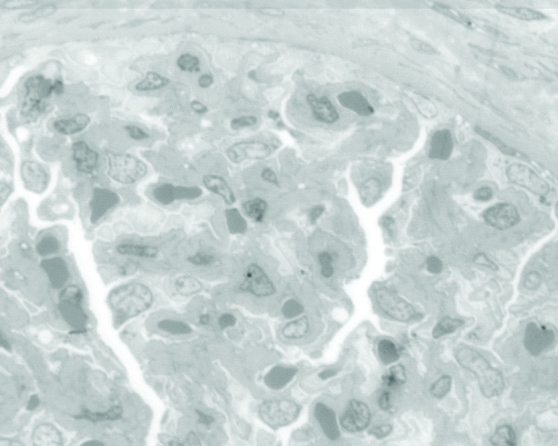

Comparison of toluidine blue staining (top) to FIRM (middle) on near adjacent sections of human kidney. Note enhanced contrast, especially of glomerular basement membranes in FIRM image. High power FIRM image (bottom) of glomerulus. Note resolution of podocyte foot processes (arrows). Scale bars in A, B, 20µm, in C, 5µm.